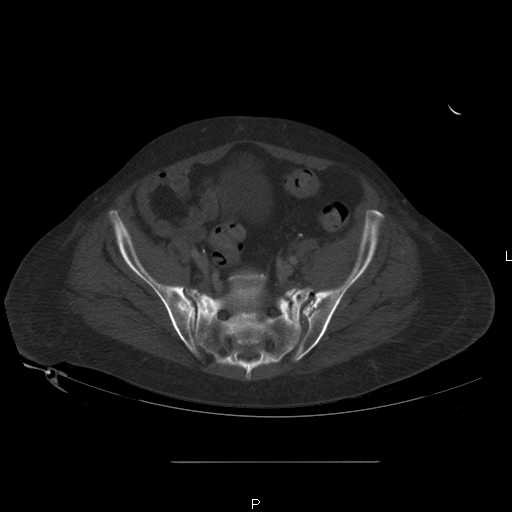

Here are a recent patient’s example slides...

54 yo Female Fell c/o Pain

Initial Films

?Instability on Exam - Limited by Pain

NonOp Initial Mgmt

3 Months After Fall

Continued Pain & Immobility

(+) Instability to Compressive Manual Exam

Pelvic CT Scan - 3 Months After Fall

Sacral Injuries

Ramus Fractures